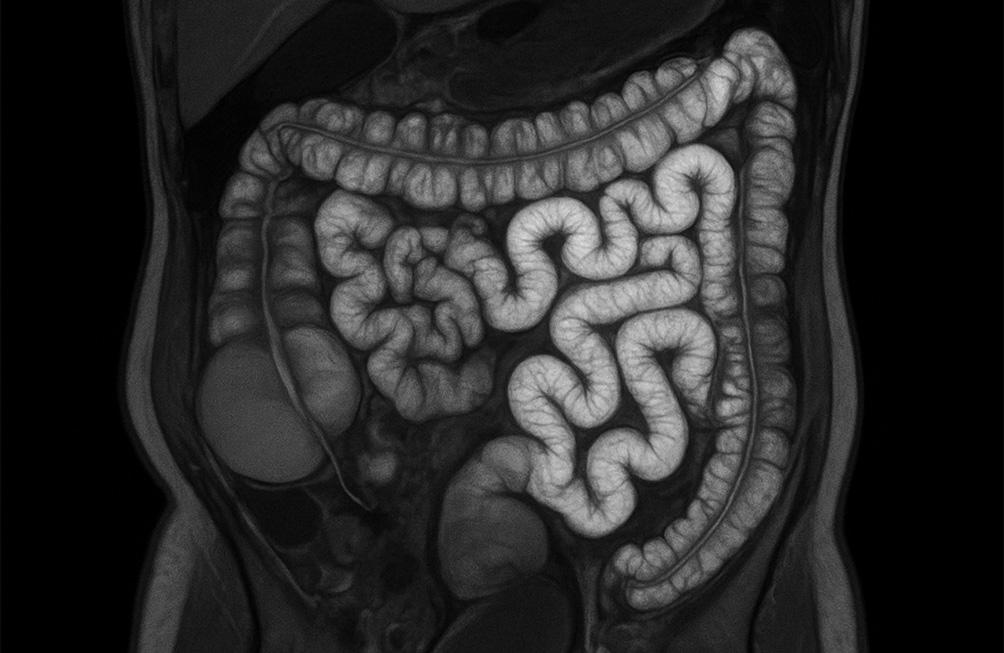

L'entéro-IRM est une méthode sûre et non invasive, réalisée afin d'examiner l'intestin, en particulier l'intestin grêle.

- Maladies inflammatoires chroniques de l’intestin (MICI) comme la maladie de Crohn ou la colite ulcéreuse, pour évaluer l’étendue, la localisation et la gravité de l’inflammation, ainsi que pour surveiller la réponse au traitement.

- Sténoses ou rétrécissements de l’intestin pour visualiser et caractériser ces anomalies.

- Complications des MICI telles que les fistules, abcès ou perforations.